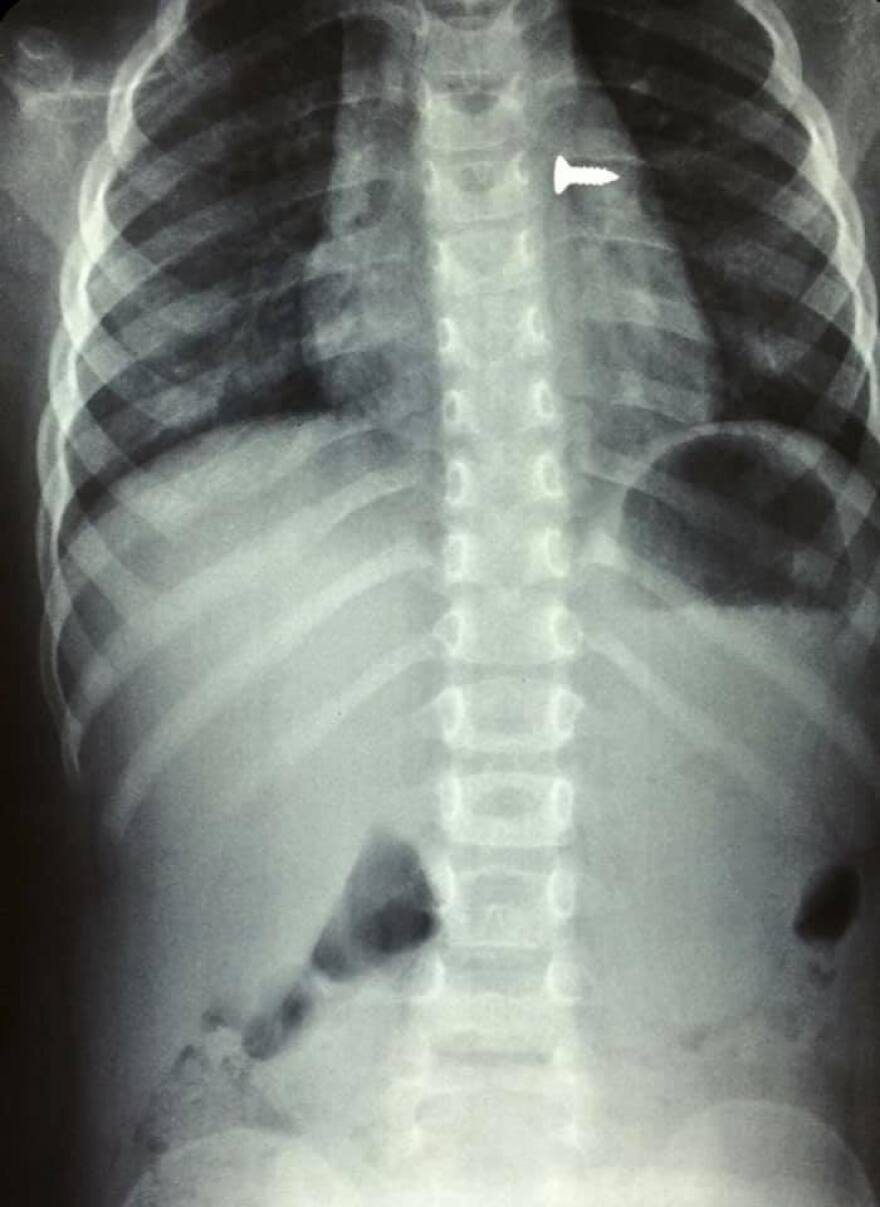

Σοκάρουν οι ακτινογραφίες από ένα κοριτσάκι στην Κρήτη που κατάπιε βίδα, η οποία κατέληξε στον αριστερό του πνεύμονα.

Σύμφωνα με τα όσα έκανε γνωστά ο αναπληρωτής καθηγητής ΩΡΛ της Ιατρικής Σχολής Κρήτης, Μανώλης Προκοπάκης, την Τρίτη μεταφέρθηκε σε νοσοκομείο του Ηρακλείου ένα τρίχρονο κορίτσι το οποίο κατάπιε μία βίδα.

Αμέσως έβγαλε ακτινογραφίες, που έδειξαν πως η βίδα βρισκόταν στον αριστερό του πνεύμονα.

Οι γιατροί οδήγησαν το κορίτσι στο χειρουργείο και μετά από αρκετή ώρα κατάφεραν να αφαιρέσουν την βίδα.

Ο κ. Προκοπάκης σε ανάρτησή του στα social media ανέφερε: «Πολύ επείγον χειρουργείο! Πριν από λίγο. Αφαίρεση βίδας από αριστερό βρογχικό δέντρο τρίχρονου κοριτσιού. Πολύ επικίνδυνο…».